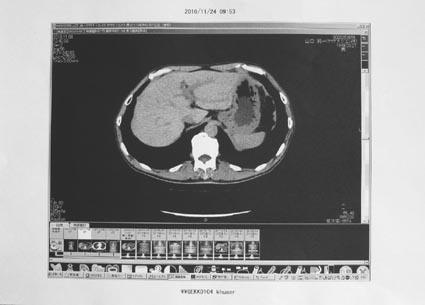

2)CT検査・下部内視鏡

<所見> 異常なし